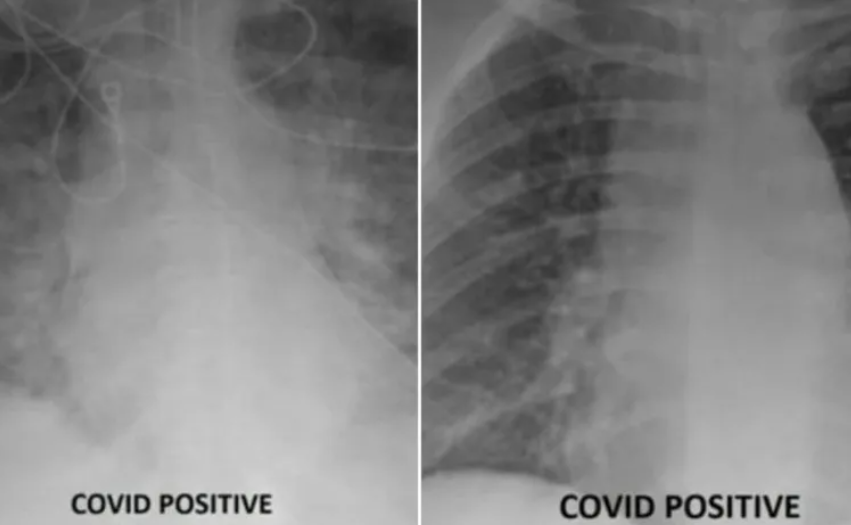

RAZLIKA JE VIDLJIVA… I ZASTRAŠUJUĆA

Ovo su snimke pluća dvije osobe zaražene Covidom: Znate li koja je osoba bila necijepljena?